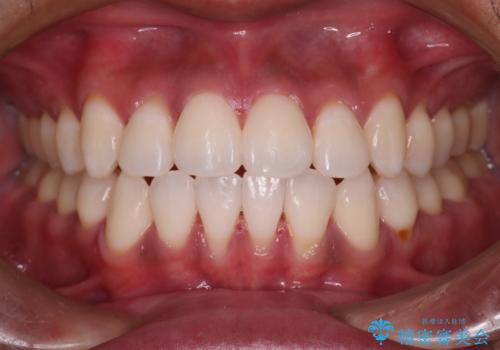

[ 奥歯の歯周病 ] エムドゲインを用いた再生治療

メンテナンスで日々のブラッシングの再確認